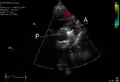

PDA

An echocardiogram of a stented persisting ductus arteriosus: One can see the aortic arch and the stent leaving. The pulmonary artery is not seen.